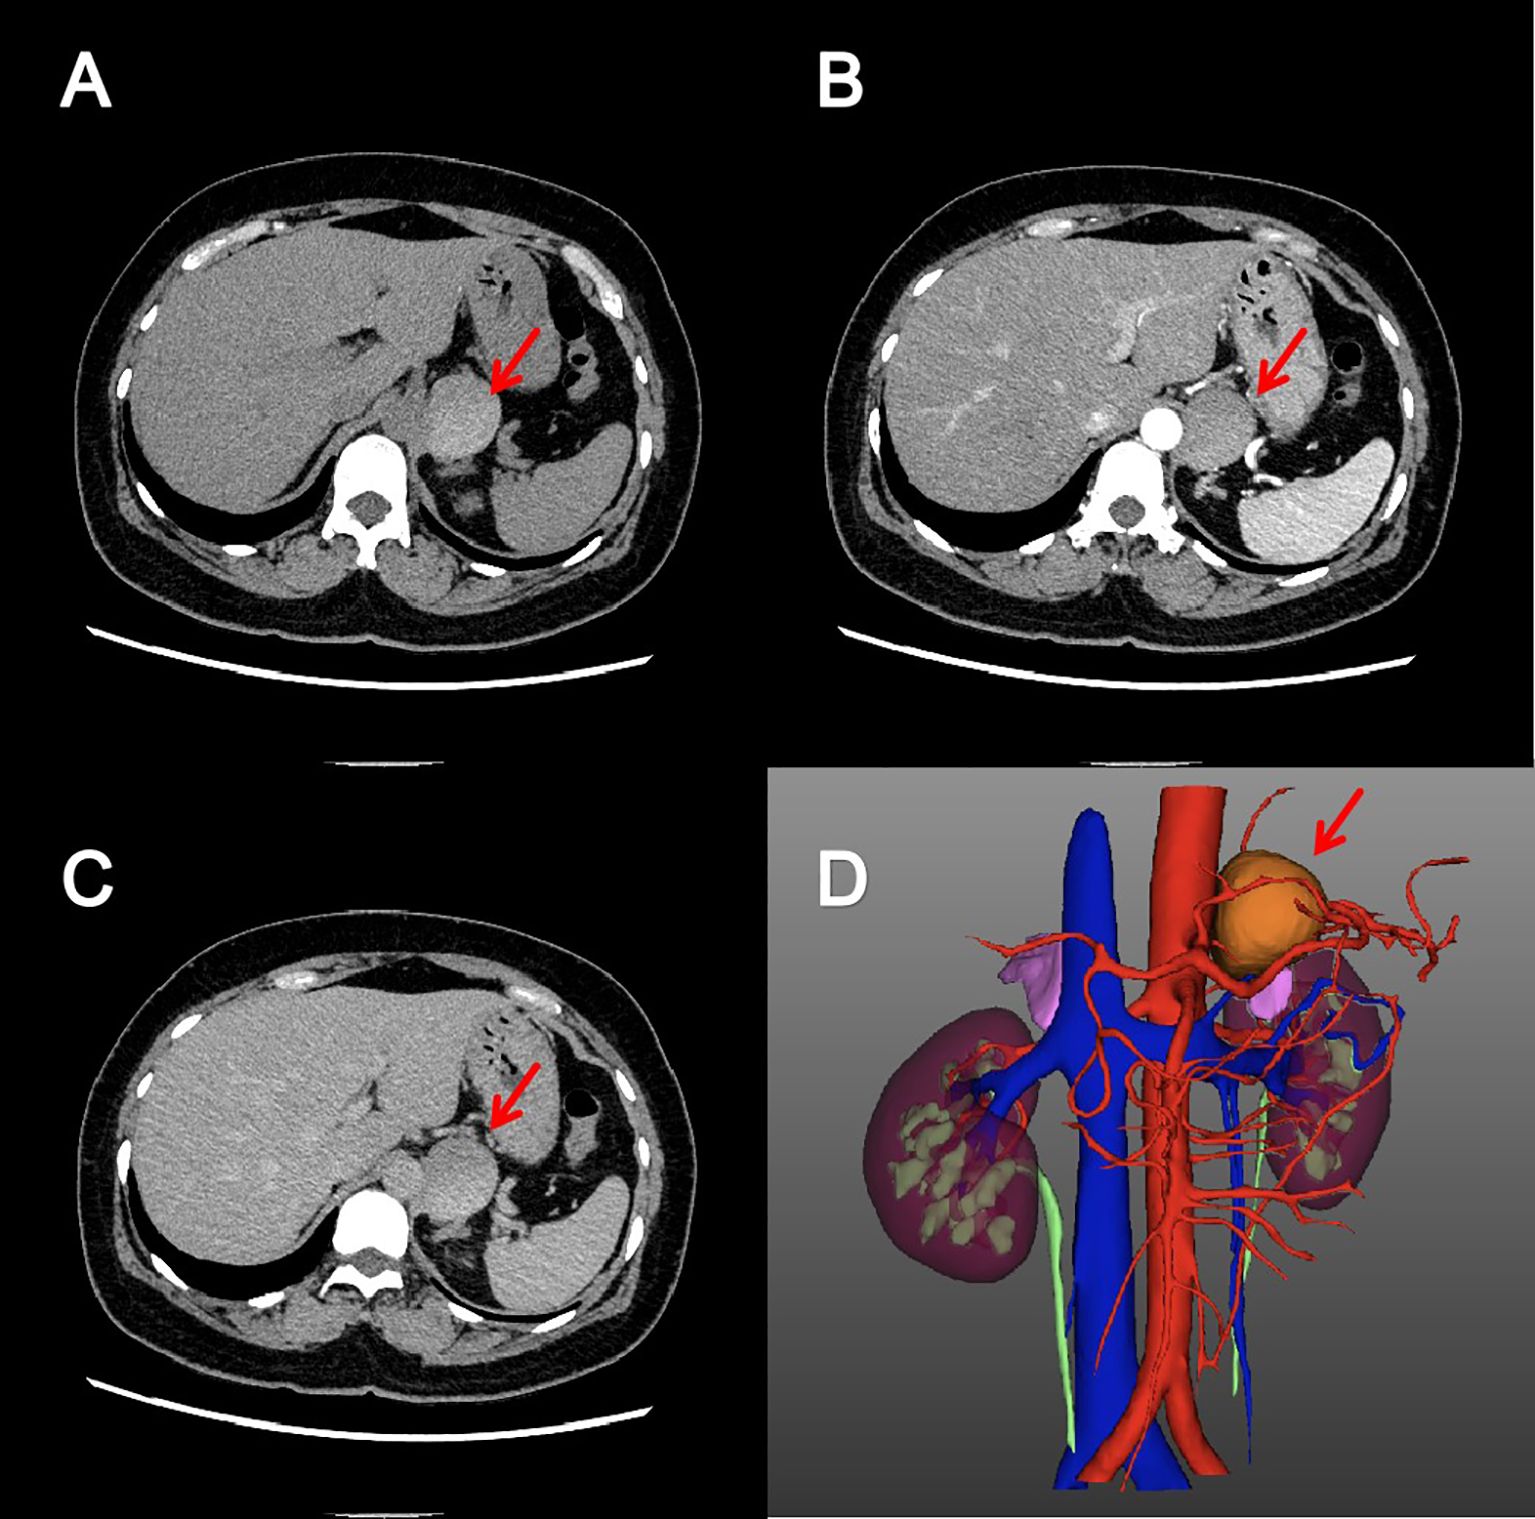

Screening for adrenal hormones, including adrenocorticotropic hormone, cortisol, and renin-aldosterone-angiotensin II levels measured at 00:00, 08:00, and 16:00, were all within normal limits. Furthermore, other biochemical studies, including complete blood count, coagulation function, liver function, renal function, serum electrolyte concentrations, and blood glucose, revealed no significant abnormalities. Key laboratory test results are shown in Table 1. Contrast-enhanced CT scan revealed a well-circumscribed, slightly hyperdense mass in the left adrenal region, measuring approximately 43×37×36 mm (Figure 1). The lesion was intimately associated with the left adrenal gland, exhibited peripheral calcification, and had a CT value of approximately 74 Hounsfield units. No significant enhancement was observed. Based on imaging characteristics, the mass was considered most consistent with a retroperitoneal cystic lesion. However, an adrenal tumor or a simple adrenal cyst could not be entirely excluded.

Figure 1. Adrenal enhanced computed tomography image. Axial pre-contrast (A), arterial phase (B) and excretory phase (C) CT images showed a cystic, well-circumscribed mass without enhancement in the left adrenal region. The reconstructed three-dimensional image (D) showed that the mass was closely related to the left adrenal gland.